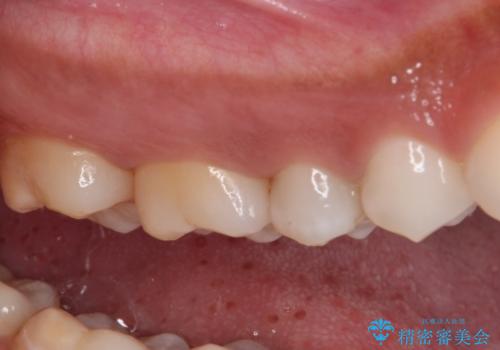

ゴールドインレーは銀歯のインレーやセラミックインレーと比べ、「技工操作の精度が高く、適合が著しく良い」というメリットがあります。特に上の奥歯は歯科医師の操作が行いにくいため、「適合の良さ」は再治療のリスクを防ぐ上でとても重要な要素となります。

上の奥歯は金属色が見えることもないため、審美的な問題は全くありません。

咬み心地はとても良好で、全く違和感がなく、患者様には大変満足していただきました。